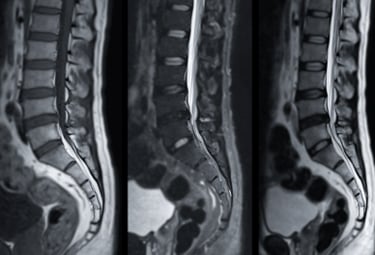

Röntgen, MR & Ultraljud

Kan vara en del av vägen till din diagnos.

Som en del av din utredning på Kroppia gör vi en noggrann klinisk bedömning av om bilddiagnostik är nödvändig för att fastställa rätt diagnos eller säkerställa att behandling kan ske tryggt.

Vi börjar alltid med en grundlig klinisk funktionsanalys. Bilddiagnostik används som ett precisionsverktyg när vi behöver bekräfta fynd eller utesluta bakomliggande orsaker som inte syns vid en manuell undersökning.

Vi går igenom dina röntgen- eller MR-svar tillsammans. Det viktigaste är hur bilderna korrelerar med din biomekaniska status, så att vi kan utforma en träffsäker behandlingsplan.

Tolkning & Åtgärd